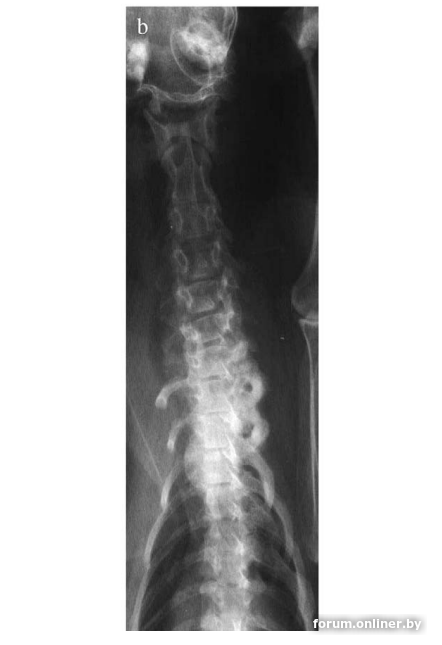

Долгосрочные эффекты витамина А проявляются после месяцев или лет избыточного потребления и характеризуются образованием обширных костных остеофитов и экзостозов вокруг суставов в местах прикрепления сухожилий, связок и суставных капсул.

В основном поражаются затылочная кость, шейные и грудные позвонки, реже - внепозвоночные участки суставов конечностей, особенно плечевых и локтевых, грудины, грудного отдела позвоночника.